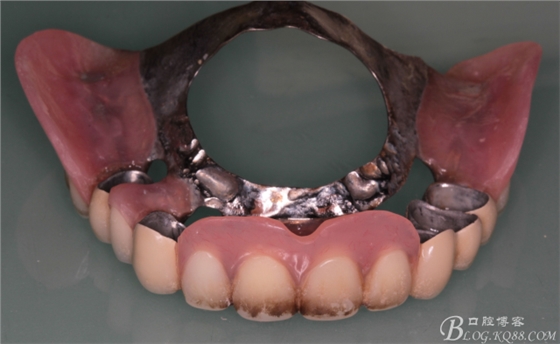

上頜基牙比較分散,選擇 5顆基牙的套筒冠修復(fù),

鈷鉻合金金屬內(nèi)冠

套筒冠外冠

修復(fù)后效果圖,